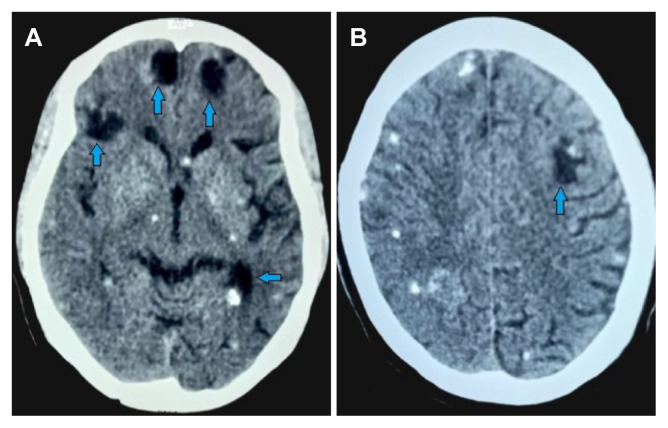

神经囊尾蚴病(NCC)是一种常见的脑寄生虫病,由摄入梭形目蛲虫卵引起,主要发生在发展中国家。在本报告中,我们介绍了一名 44 岁女性的病例,她表现出中风症状,并有长达十年的反复头痛和癫痫病史。就诊时,她接受了脑部非对比计算机断层扫描,结果显示两侧大脑半球均有密度过低的椭圆形病变和钙化囊肿,这强烈提示她患有 NCC。患者对地塞米松、阿苯达唑和卡马西平的治疗反应良好。本病例研究强调了神经影像学在调查癫痫等神经系统疾病患者时的重要性,尤其是在发展中国家。早期诊断和有效治疗对于预防和控制 NCC,减少其对公众健康的影响至关重要。

Neurocysticercosis (NCC) is a common parasitic brain infestation caused by the ingestion of Taenia solium eggs, predominantly in developing countries. In this report, we presented the case of a 44-year-old woman who exhibited stroke symptoms and had a decade-long history of recurrent headaches and epilepsy. At presentation, a non-contrast computed tomography scan of the brain was performed and revealed hypodense oval lesions and calcified cysts in both cerebral hemispheres, strongly indicative of NCC. The patient responded positively to treatment with dexamethasone, albendazole, and carbamazepine. This case study underscores the importance of neuroimaging in investigating patients with neurological conditions like epilepsy, especially in developing countries. Early diagnosis and effective treatment are crucial in preventing and controlling NCC, reducing its impact on public health.